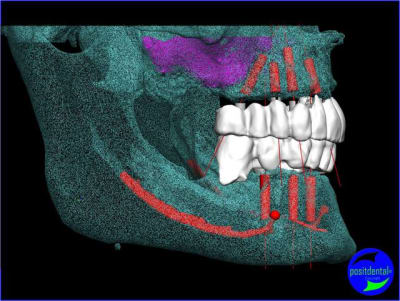

projet implantaire pour février

1er étape le wax-Up, dans ce cas clinique il est réalisé en 3D

Cette vidéo présente une gestion de l'esthétique dans un cas d'extraction, implantation, mise en charge immédiate alors qu’il ne reste pas de chicot mais des dents mobiles.

un autre exemple d'extraction implantation au maxillaire

Depuis + de 10 ans Positdental a développé des solutions technique pour indexer le pilier prothétiques lorsque l'implant est angulé, une des réalisations en 2008.